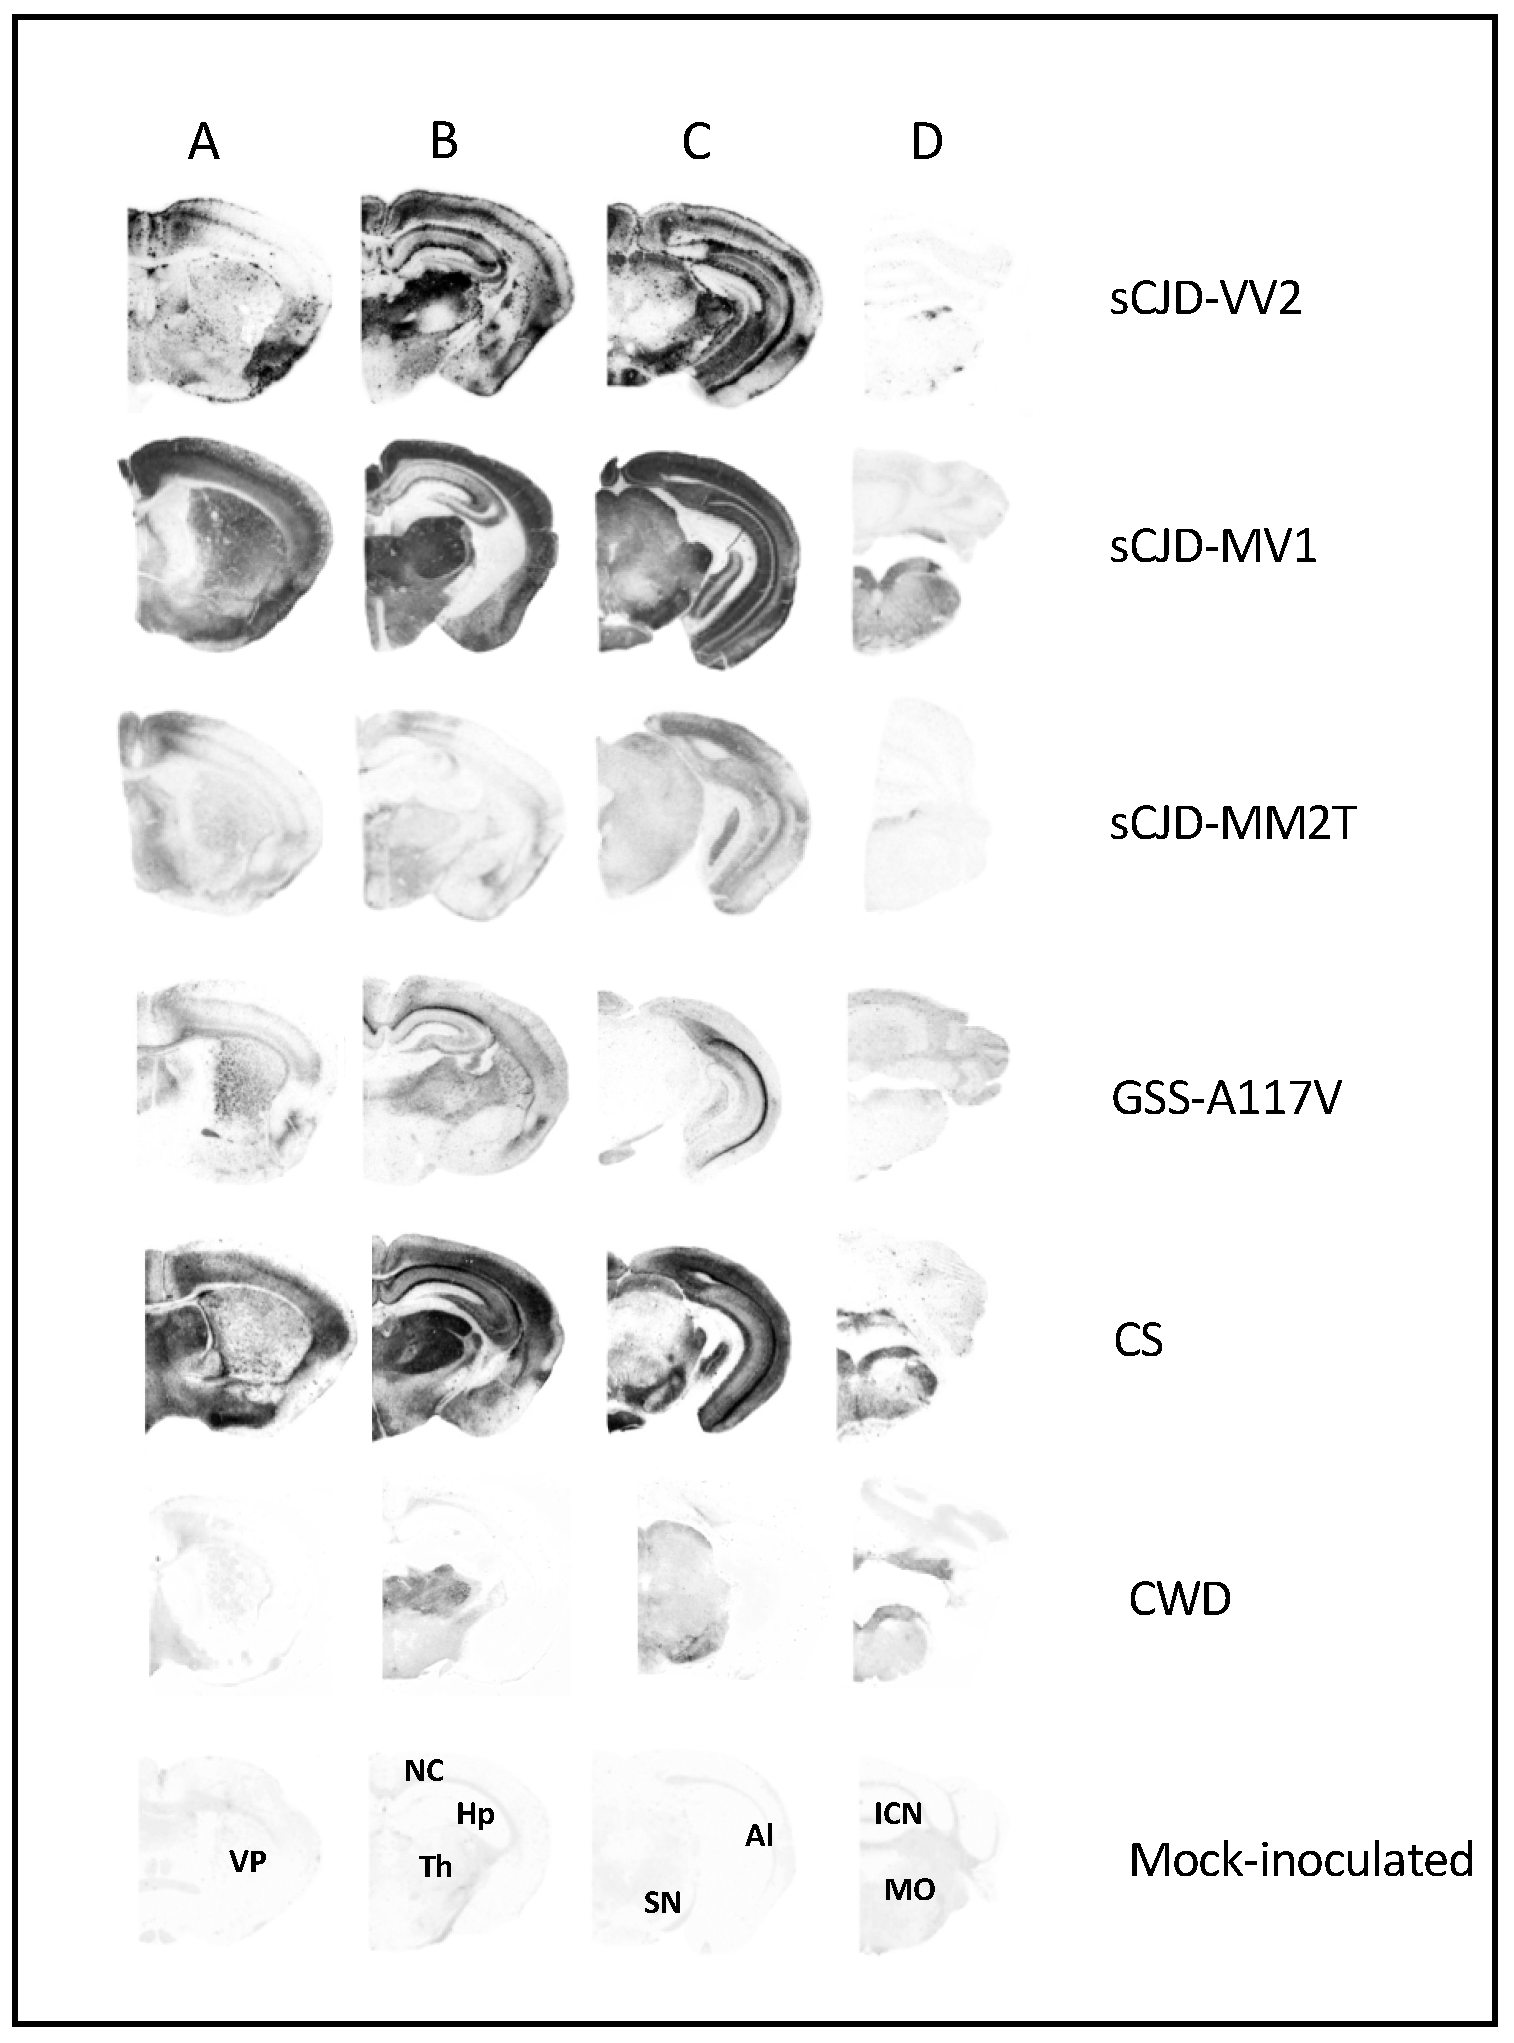

3.1. Characterization of Vole-Adapted Strains